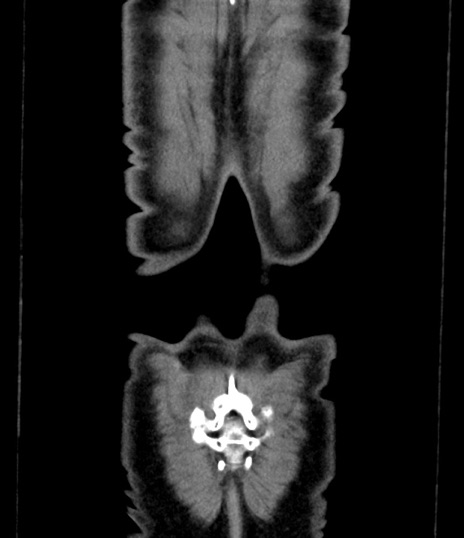

症例8(冠状断像)

横断像